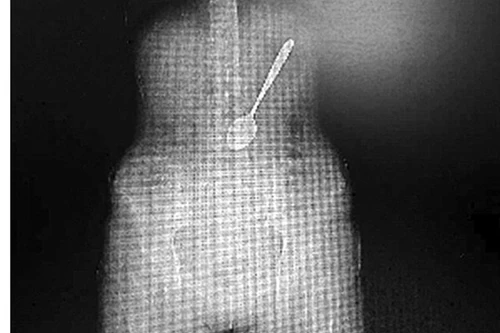

Ăn mỳ, nuốt luôn cả thìa